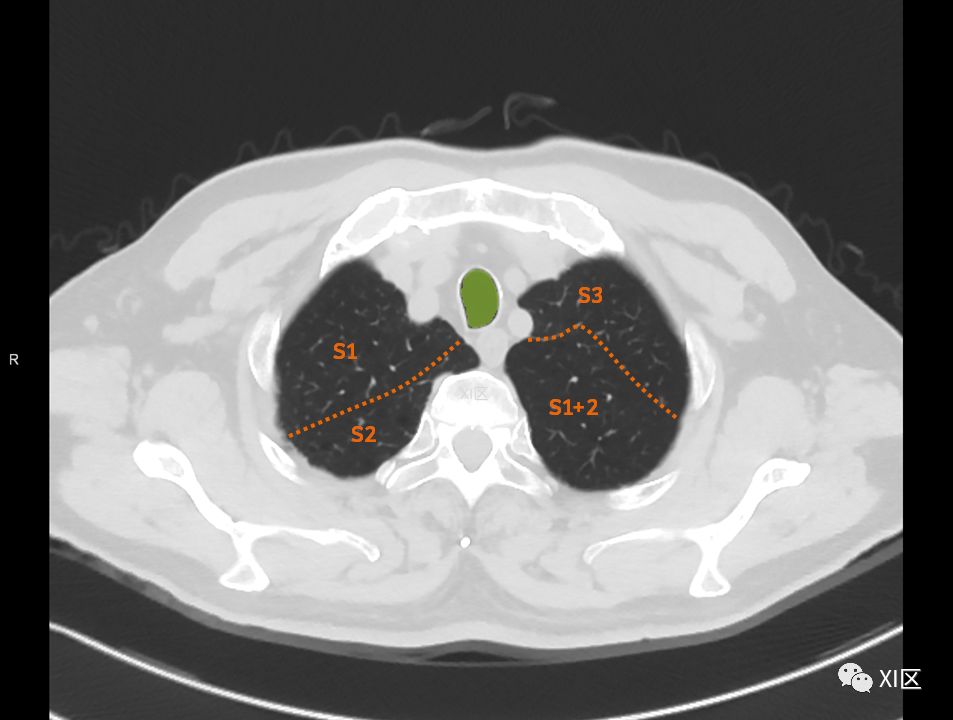

肺的分段

肺的断层分段示意图

在进行肺的分段时,可以上下观察浏览,沿着相应气管的走形可以更容易准确地进行分段。